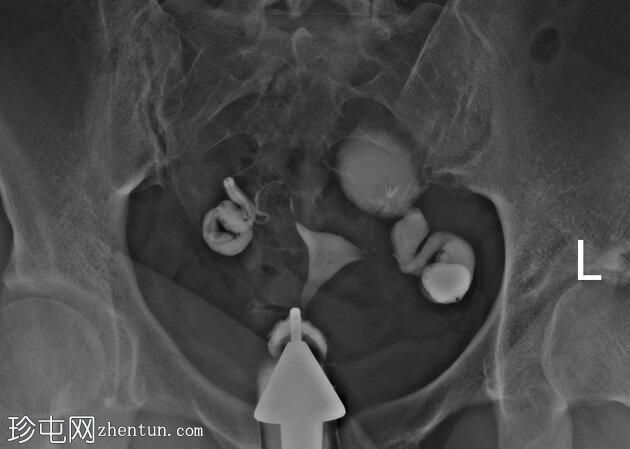

子宫体位于盆腔中线,形态及轮廓正常。

宫颈管长度正常,黏膜表面扩张良好。

右侧输卵管扩张并充满液体,无腹膜溢出,提示输卵管积水及输卵管阻塞。

左侧输卵管亦扩张并充满液体,伴有造影剂残留及少量溢出,提示输卵管积水及输卵管阻塞。

此外,左侧盆腔内,位于输卵管上内侧,可见大量分隔的造影剂积聚,并伴有盆腔输卵管周围粘连。

子宫输卵管造影结果符合双侧输卵管阻塞和输卵管积水,左侧输卵管周围可见分隔的造影剂渗漏。